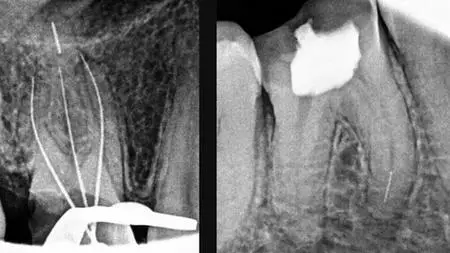

Management Of Separated Endodontic Instrument

Causes of instrument separation, Bypassing, broken instrument retrieval